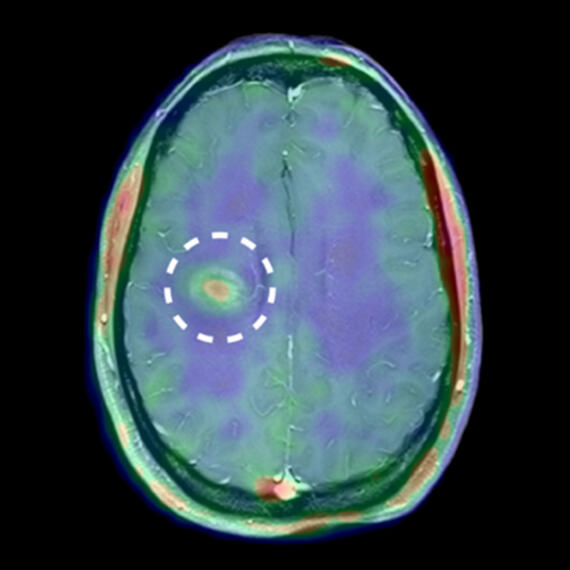

MMP-Aktivität im Gehirn eines MS-Patienten

© Gerwien & Hermann et al., Sci. Transl. Med. 8, 364ra152 (2016) 9 November 2016

Molecular mechanisms and in vivo tracking of leukocyte penetration of the blood-brain barrier (BBB) in autoimmune CNS inflammation

Wir untersuchen die Funktion der Proteine MMP-2 und MMP-9 an der Blut-Hirn-Schranke. Unser Ziel ist es, die MMP-Aktivität zu nutzen, um Leukozyten sichtbar zu machen, die die Blut-Hirn-Schranke durchdringen. Diese spielen bei der Multiplen Sklerose eine Rolle, wenn Immunzellen ins Gehirn wandern und dort Entzündungen verursachen.